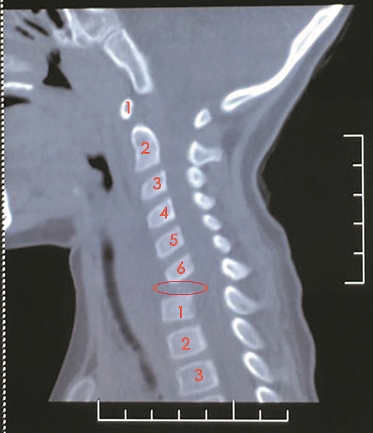

颈椎CT:红圈所在位置为琦琦缺失的颈7椎体。

到底怎么回事?琦琦被送到医院检查,结果让人大吃一惊,琦琦患上的是“颈椎结核”!影像学检查发现她颈7椎体周围有大量脓肿,而且那一节颈椎的骨质已被结核杆菌吞噬得“面目全非”,就好像“消失”了一样。

6月4日这天,吴增晖为琦琦实施手术。他从琦琦病变的颈椎处,取出了已被腐蚀得呈“啫喱”状的颈7椎体,手术团队随后彻底清除了结核病灶和周围的脓性分泌物,并从琦琦的髂骨处取了和颈椎大小一样的骨头,填补在空缺的颈椎处,用特殊的钢板和钉子将颈椎固定住。整个手术时间不到2小时,出血仅5毫升。